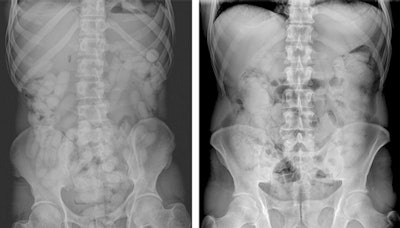

Initial modalities for detection of any drugs concealed within the body include x-ray, and ultrasound, but these are sometimes insufficient and can yield false-negative and false-positive results, while other legal and ethical considerations must also be factored into attempts at diagnosis.

In each radiological examination method, it is important to know how packets containing different materials can be visualized. For example, liquid cocaine is radiopaque with thin lucent lines on plain film, and on ultrasound has a hyperechoic irregular surface with clean shadow. However, on CT it appears hyperdense with thin hypodense lines and a specific jigsaw pattern.